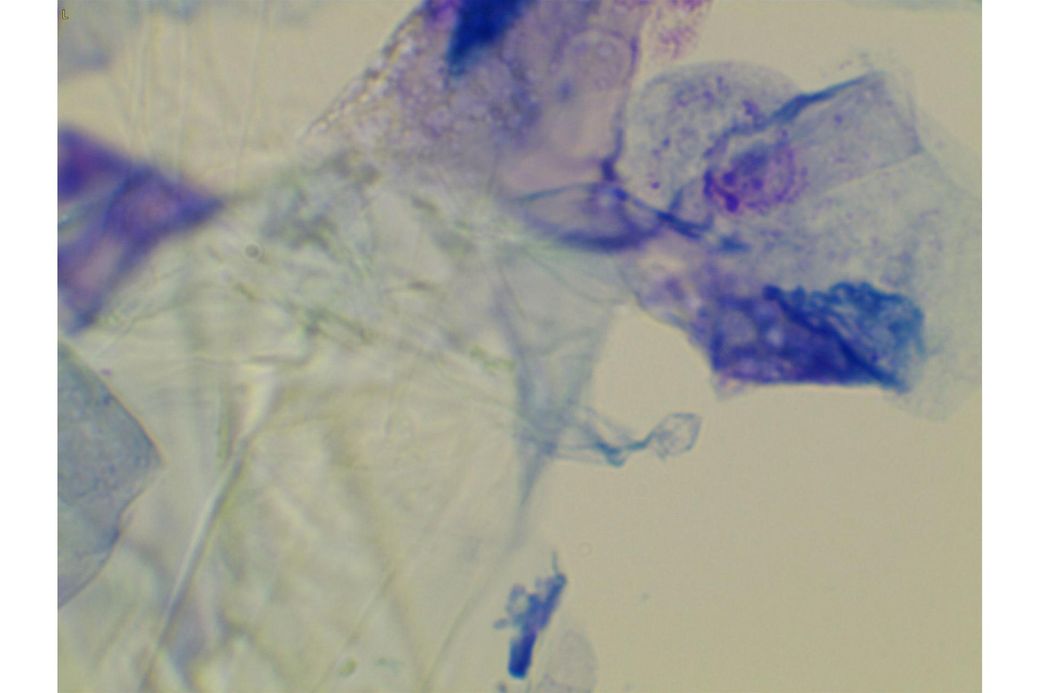

오늘 낮과 방금 5분전에 일어난 일인데요.. 강아지 귀질환 중에.. 옷입히고나서 귀를 바닥에 대고 비비거나, 귀에 통증을 호소하면서 잠깐 비틀비틀 걷는 경우 이런 경우 대체 뭘까요? 외이염일때도 이럴수도 있을까요? 아니면 중이염 내이염일지.. 한 2~3분정도 통증을 호소하다 지금은 또 정상이 됬는데 옷입을때만 옷의 목카라 부분이 귀에 닿을때 문제가 되는 느낌입니다. 평상시엔 가끔 양쪽 귀를 긁거나 귀를 자주 터는 정도입니다. 특이사항은 오른쪽귀 솜 돌돌 말아 귀안에 넣어줘도 비명을 지르며 엄청 아파하는데(작년11월경) 왼쪽은 안아파합니다)

mri ct 말고는 죽어도 중이염 내이염 또는 고막 확인이 불가능한가요?

제가 가장 알고싶은점은. 저렇게 옷깃에 귀가 시쳐도 아파할정도면 이게 외이염일까요 중이염일까요 내이염일까요? 얼마나 아픈지 옷한번 얇은 내복 평상시 입던거 입히면 입히고 나서 바로 온집을 돌아다니면서 바닥에 귀를 대고 정신나간애처럼 비비고 비틀비틀 걷습니다 그러다가 2~3분후 다시 정상으로 돌아옵니다